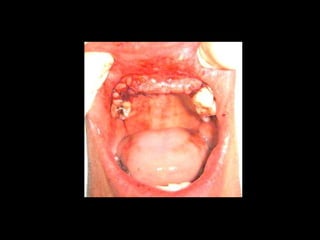

Plastia de maxilares para implantes dentales.

Plastia alveolar con factores de crecimiento y

traspalnate de hueso cadaverico

La conformación quirúrgica de un contorno alveolar adecuado es

determinante para la correcta aplicación y aceptación de los implantes

de titanio, aquí proponemos una técinica para lograr el espesor óseo

suficiente y la corrección estética del proceso, ya que antiguamente al

extraer un diente se acostumbraba presionar las tablas alveolares

“para cohibir la hemorragia”, con el colapso subsiguiente de la región.

La aplicación de implantes requiere de una cantidad y calidad de hueso

Importantes para sostener el metal en un área de estroma óseo

Saludable. Esto se logra efectuando una valoración adecuada de las

Características sistémicas del paciente y no injertando hueso o haciendo

Plastías indiscriminadamente.

He dado algunas directrices en el área de “consideraciones sobre

Implantes”

Este tipo de procedimientos puede considerarse como una forma de cirugía

preprotésica, la cual debe efectuarse con un conocimiento integral de las

alteraciones locales y sistémicas del paciente.

En mi práctica he observado el entusiasmo simplista de muchos odontólogos

practicando este tipo de intervenciones en pacientes con padecimientos que

afectan directamente al hueso (vejez, osteoporosis, diabetes, tumores óseos, etc.)

De ahí mi invitación a que estos procedimientos se efectúen apoyándose en

personas que hayan tenido un entrenamiento hospitalario a nivel de Residencia en

Cirugía Máxilofacial.